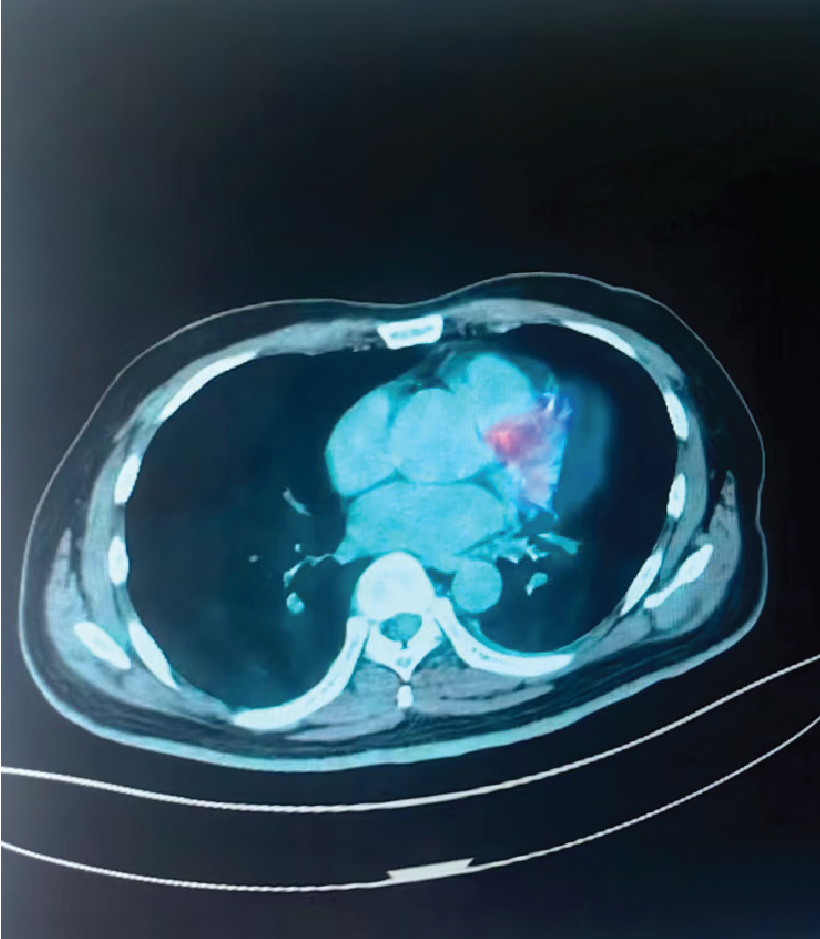

Before Treatment (Lung)

2-Month Follow-Up